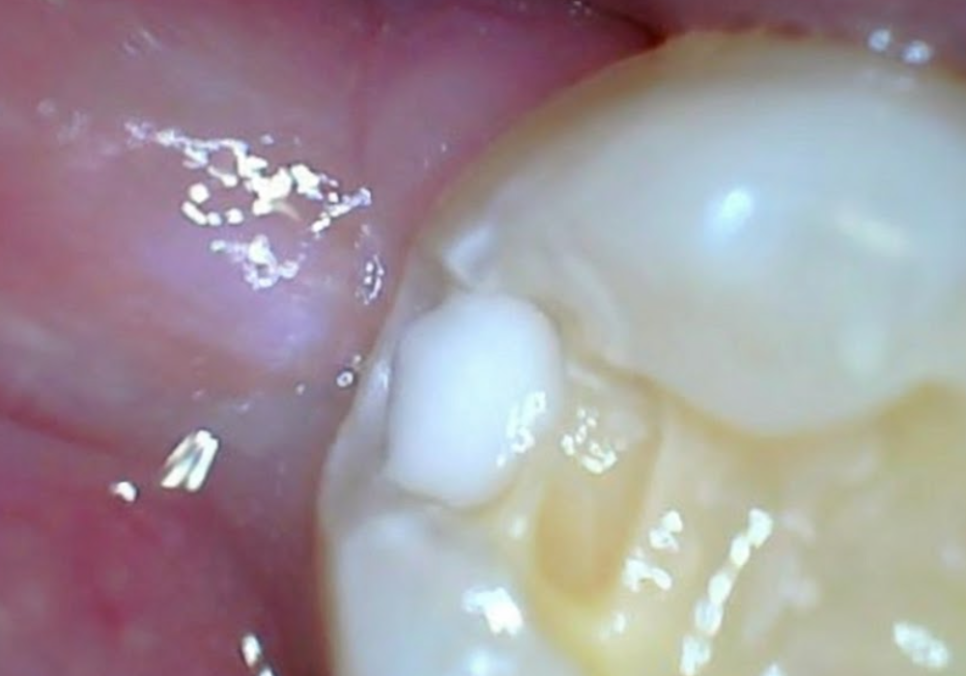

하지만, 진짜 문제는

사랑니를 뽑고 나서 드러났습니다.

221231

그동안 사랑니에 가려져 보이지 않던

앞 치아의 뒷면이 새까맣게 썩어 있었거든요.

사랑니가 찰싹 붙어있던 자리에

음식물 찌꺼기들이 쌓이면서,

앞 치아의 옆구리가 야금야금 썩어 들어간 거죠.

씹는 면이 아닌,

치아 옆면이기 때문에 잇몸에 가려져 있어서

그동안 발견하기가 참 어려웠을 거예요.